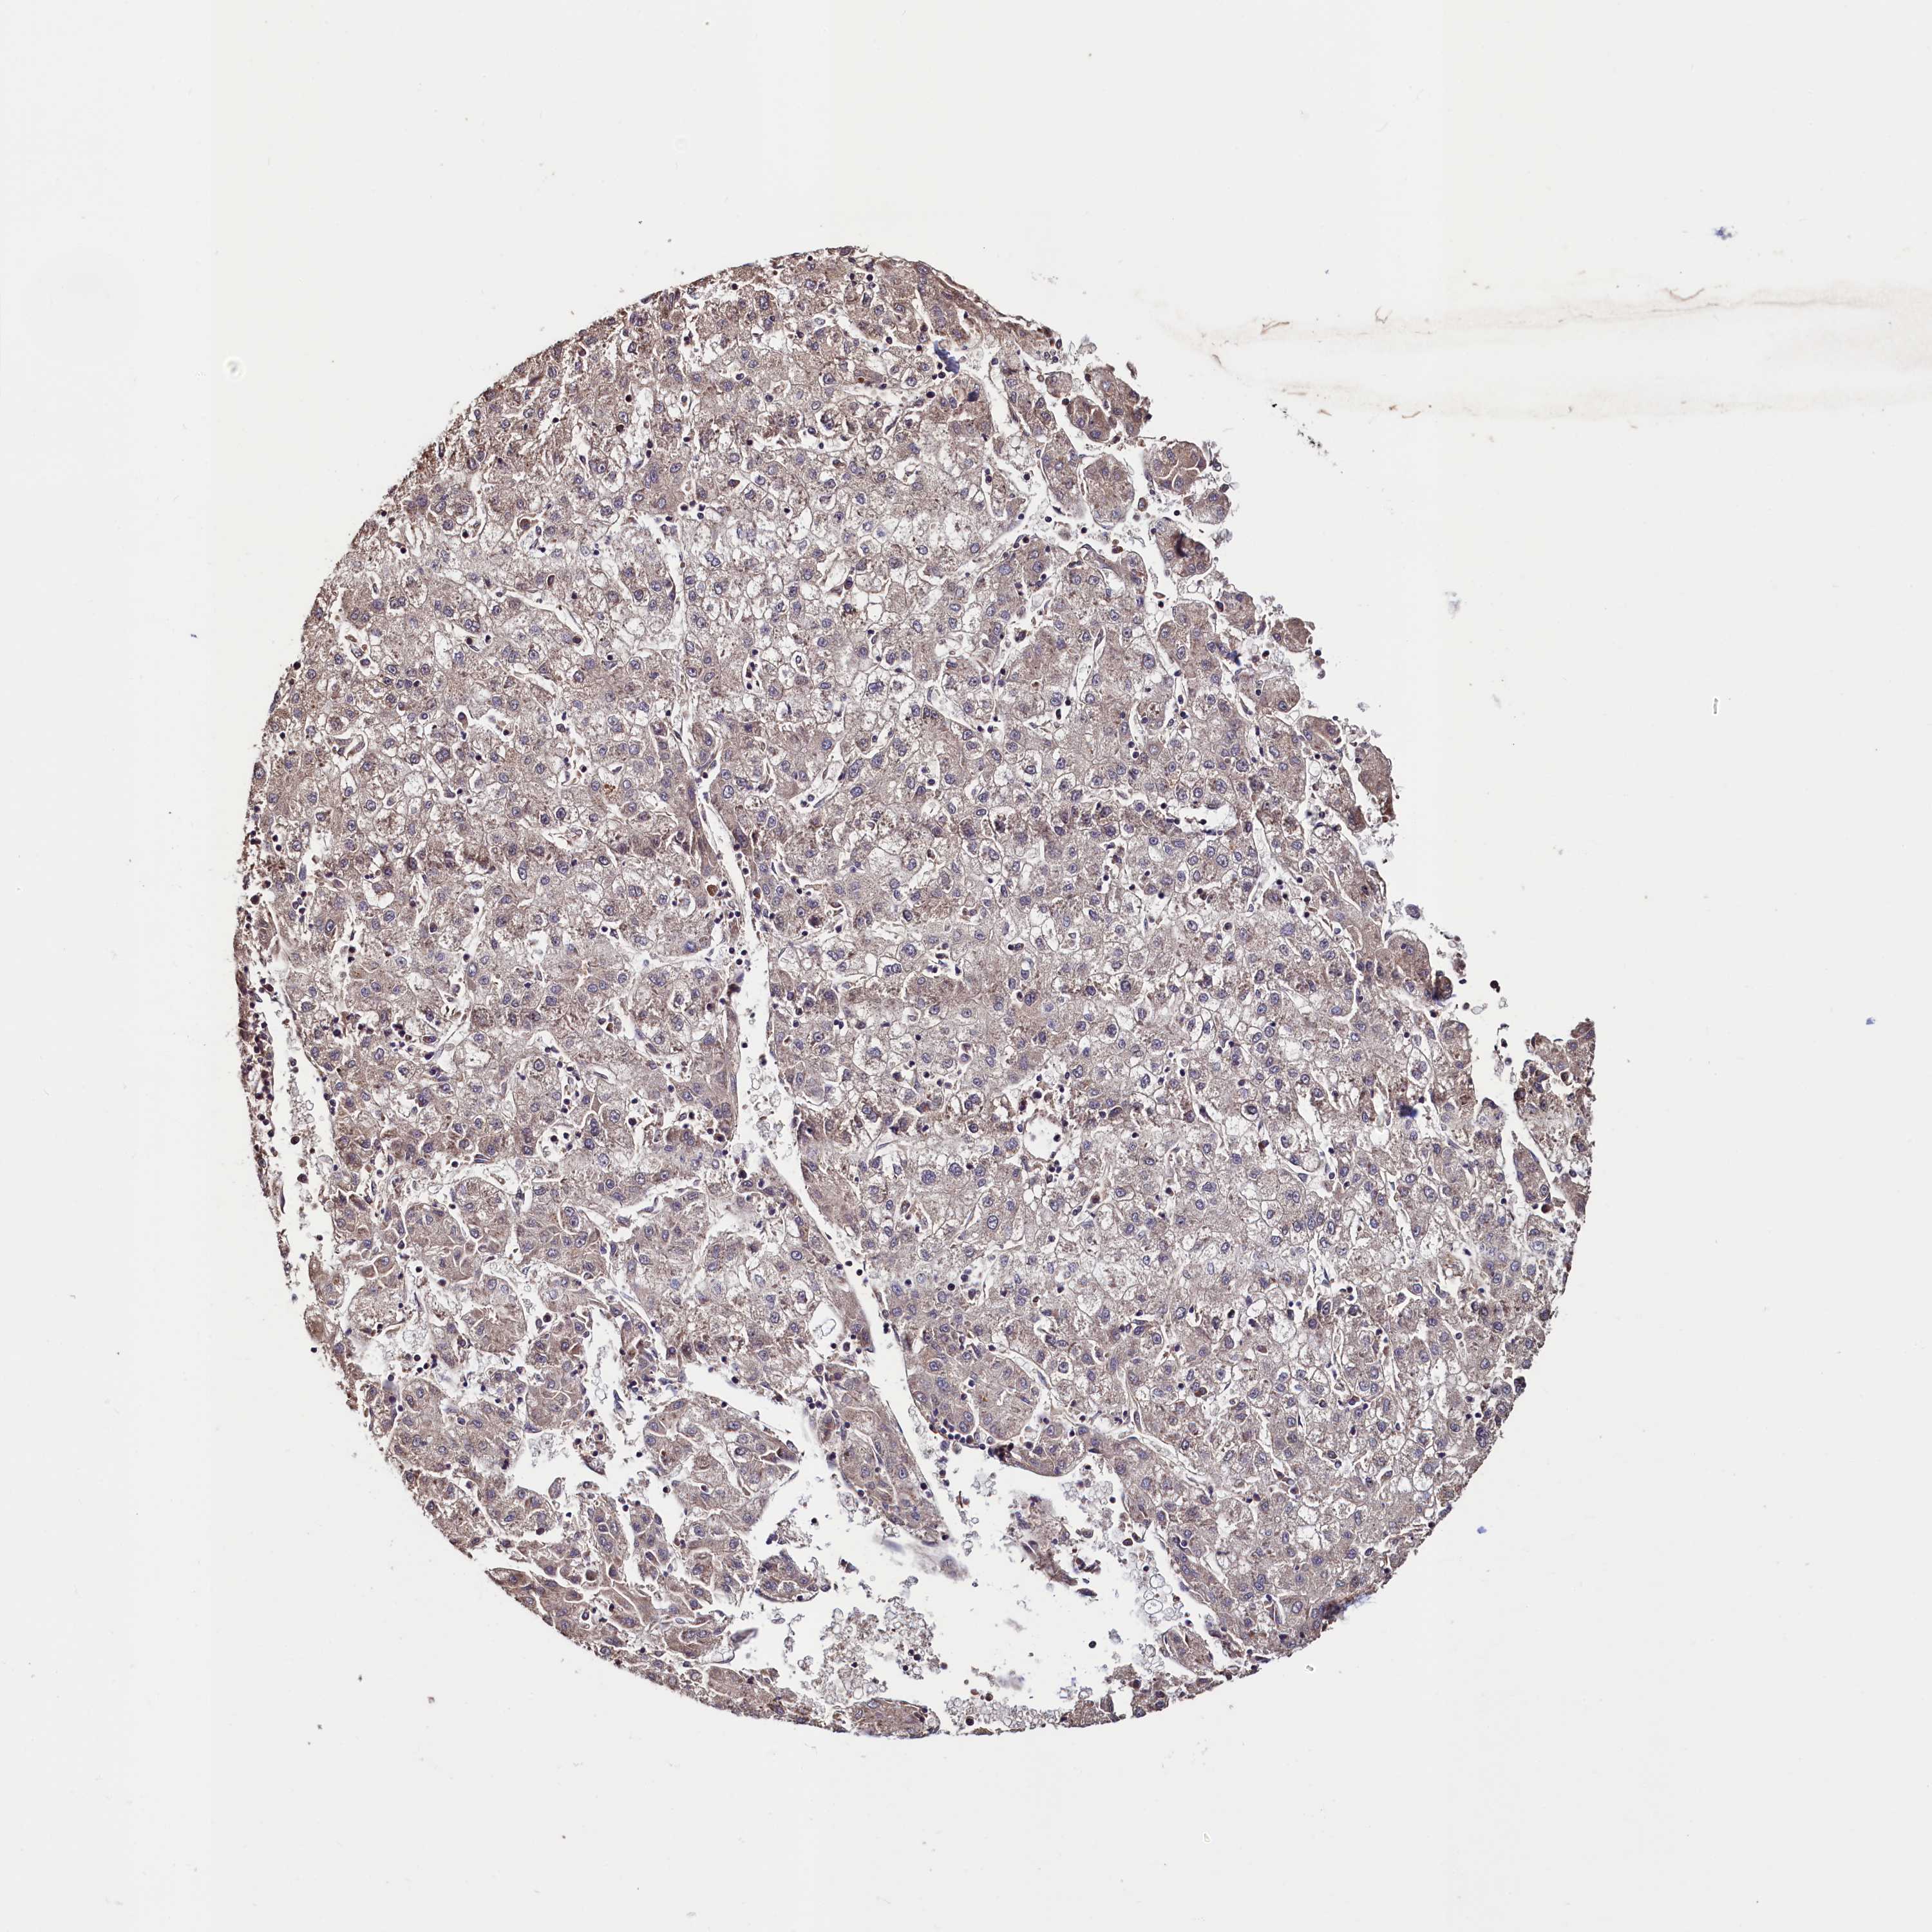

LIVER CANCER - Protein expressioni

A mouse-over function shows sample information and annotation data. Click on an image to view it in a full screen mode. Samples can be filtered based on level of antibody staining by selecting one or several of the following categories: high, medium, low and not detected. The assay and annotation is described here.

Note that samples used for immunohistochemistry by the Human Protein Atlas do not correspond to samples in the TCGA dataset.

Antibody stainingi

Antibody staining in the annotated cell types in the current human tissue is reported as not detected, low, medium, or high, based on conventional immunohistochemistry profiling in selected tissues. This score is based on the combination of the staining intensity and fraction of stained cells.

Each image is clickable and will lead to virtual microscopy that enables deeper exploration of all samples and also displays staining intensity scores, fraction scores and subcellular localization as well as patient and tissue information for each sample.

Antibody HPA040485

Antibody HPA041479

Staining

High

Medium

Low

Not detected

Intensity

Strong

Moderate

Weak

Negative

Quantity

>75%

75%-25%

<25%

None

Location

Nuclear

Cytoplasmic/membranous

Cytoplasmic/membranous,nuclear

Cholangiocarcinoma

Carcinoma, Hepatocellular, NOS